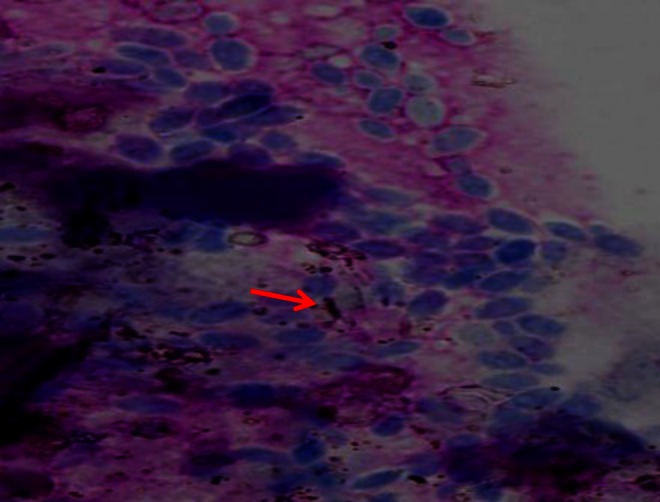

Cytological examination impression smears stained by Leishman’s stain revealed a large number of budding yeast-like organisms and early pseudohyphae (Fig. 2), suggesting Candida as an etiological agent and, hence, the disease thrush.

Fig. 2.

Large number of yeast-like organisms and early pseudohyphae (red arrow)